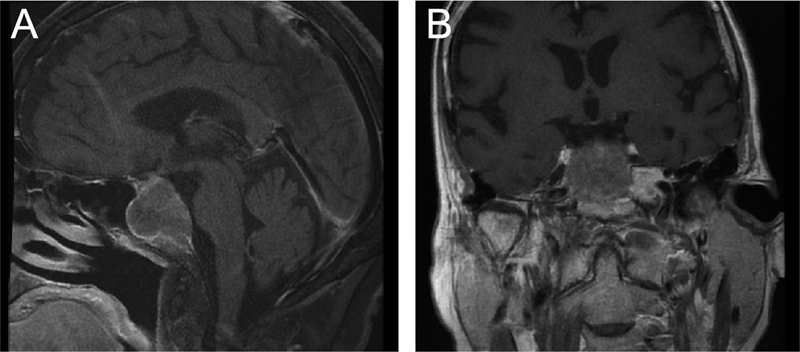

Introduction  Clival tumors are rare and heterogeneous. Although some benign prototypical sellar lesions may present as clival tumors, the likelihood of malignant disease is higher. Here we define a novel algorithm for the workup and management of clival masses through an illustrative case of colorectal adenocarcinoma metastasis to the clivus. Methods  In this case report, the best practice guidelines for managing clival masses are described through a literature review and refined by senior author consensus. We conducted a focused systematic review to characterize the present case in the context of clival metastasis from gastrointestinal malignancy. Results  An 83-year-old woman presented with 4 weeks of headaches and blurry vision. Examination revealed partial right abducens and left oculomotor palsies. Magnetic resonance imaging (MRI) identified a large, weakly enhancing sellar and clival mass with sphenoid sinus extension. An aggressive subtotal endoscopic endonasal resection was performed with removal of all sphenoid, clival, and sellar disease without cavernous sinus wall resection. Pathology confirmed colorectal adenocarcinoma; computed tomography (CT) imaging identified an ascending colon mass with metastases to the liver and mesenteric nodes. Palliative oncologic therapies were recommended, but she elected hospice, and died 3 months after initial presentation. Gastrointestinal clival metastases are exceedingly rare among sellar and clival pathologies, with eight prior cases reported, most of which presented with diplopia from abducens nerve involvement. Conclusion  Clival masses are uncommon skull base lesions that are associated with more aggressive diseases. We present a consolidated framework for decision-making in these challenging patients, alongside an unusual case example that illustrates the importance of increased suspicion for malignant clinical entities in this setting.